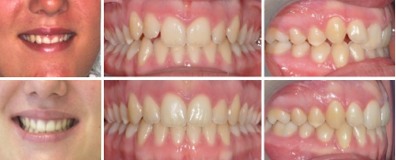

Fall 3: Aufgewanderte Zahnreihe

Therapie: Spezialapparatur zum zurückschieben der Zähne und Gartenhag nur im Oberkiefer notwendig